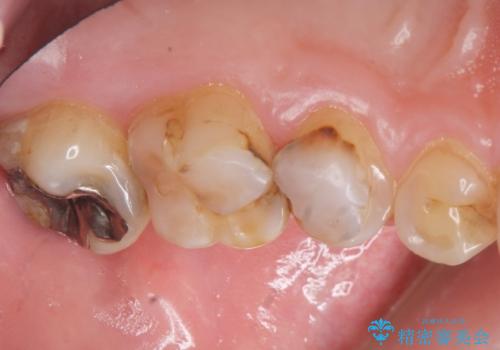

- K-POP(Kポップ)アイドルのような歯にしたいと希望され来院された患者様です。

矯正を途中でやめてしまったとのことで、歯に矯正の接着材が残っており着色も顕著でした。

奥歯の咬合面にはレジンが盛られた状態でした。